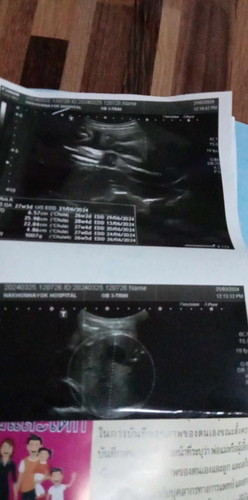

หนูอายุ14 พึ่งเคยท้องอยากรู้ว่าดูยังไงค่ะ 30 สัปดาห์ 5 วันค่ะ

โดยปกติอายุครรภ์มากแล้ว ถ้าน้องไม่หนีบ คุณหมอน่าจะแจ้งแล้วนะคะ ในภาพจะไม่ใช่หว่างขาของน้องเลยทำให้ดูไม่ออกว่าเพศอะไรค่ะ☺️